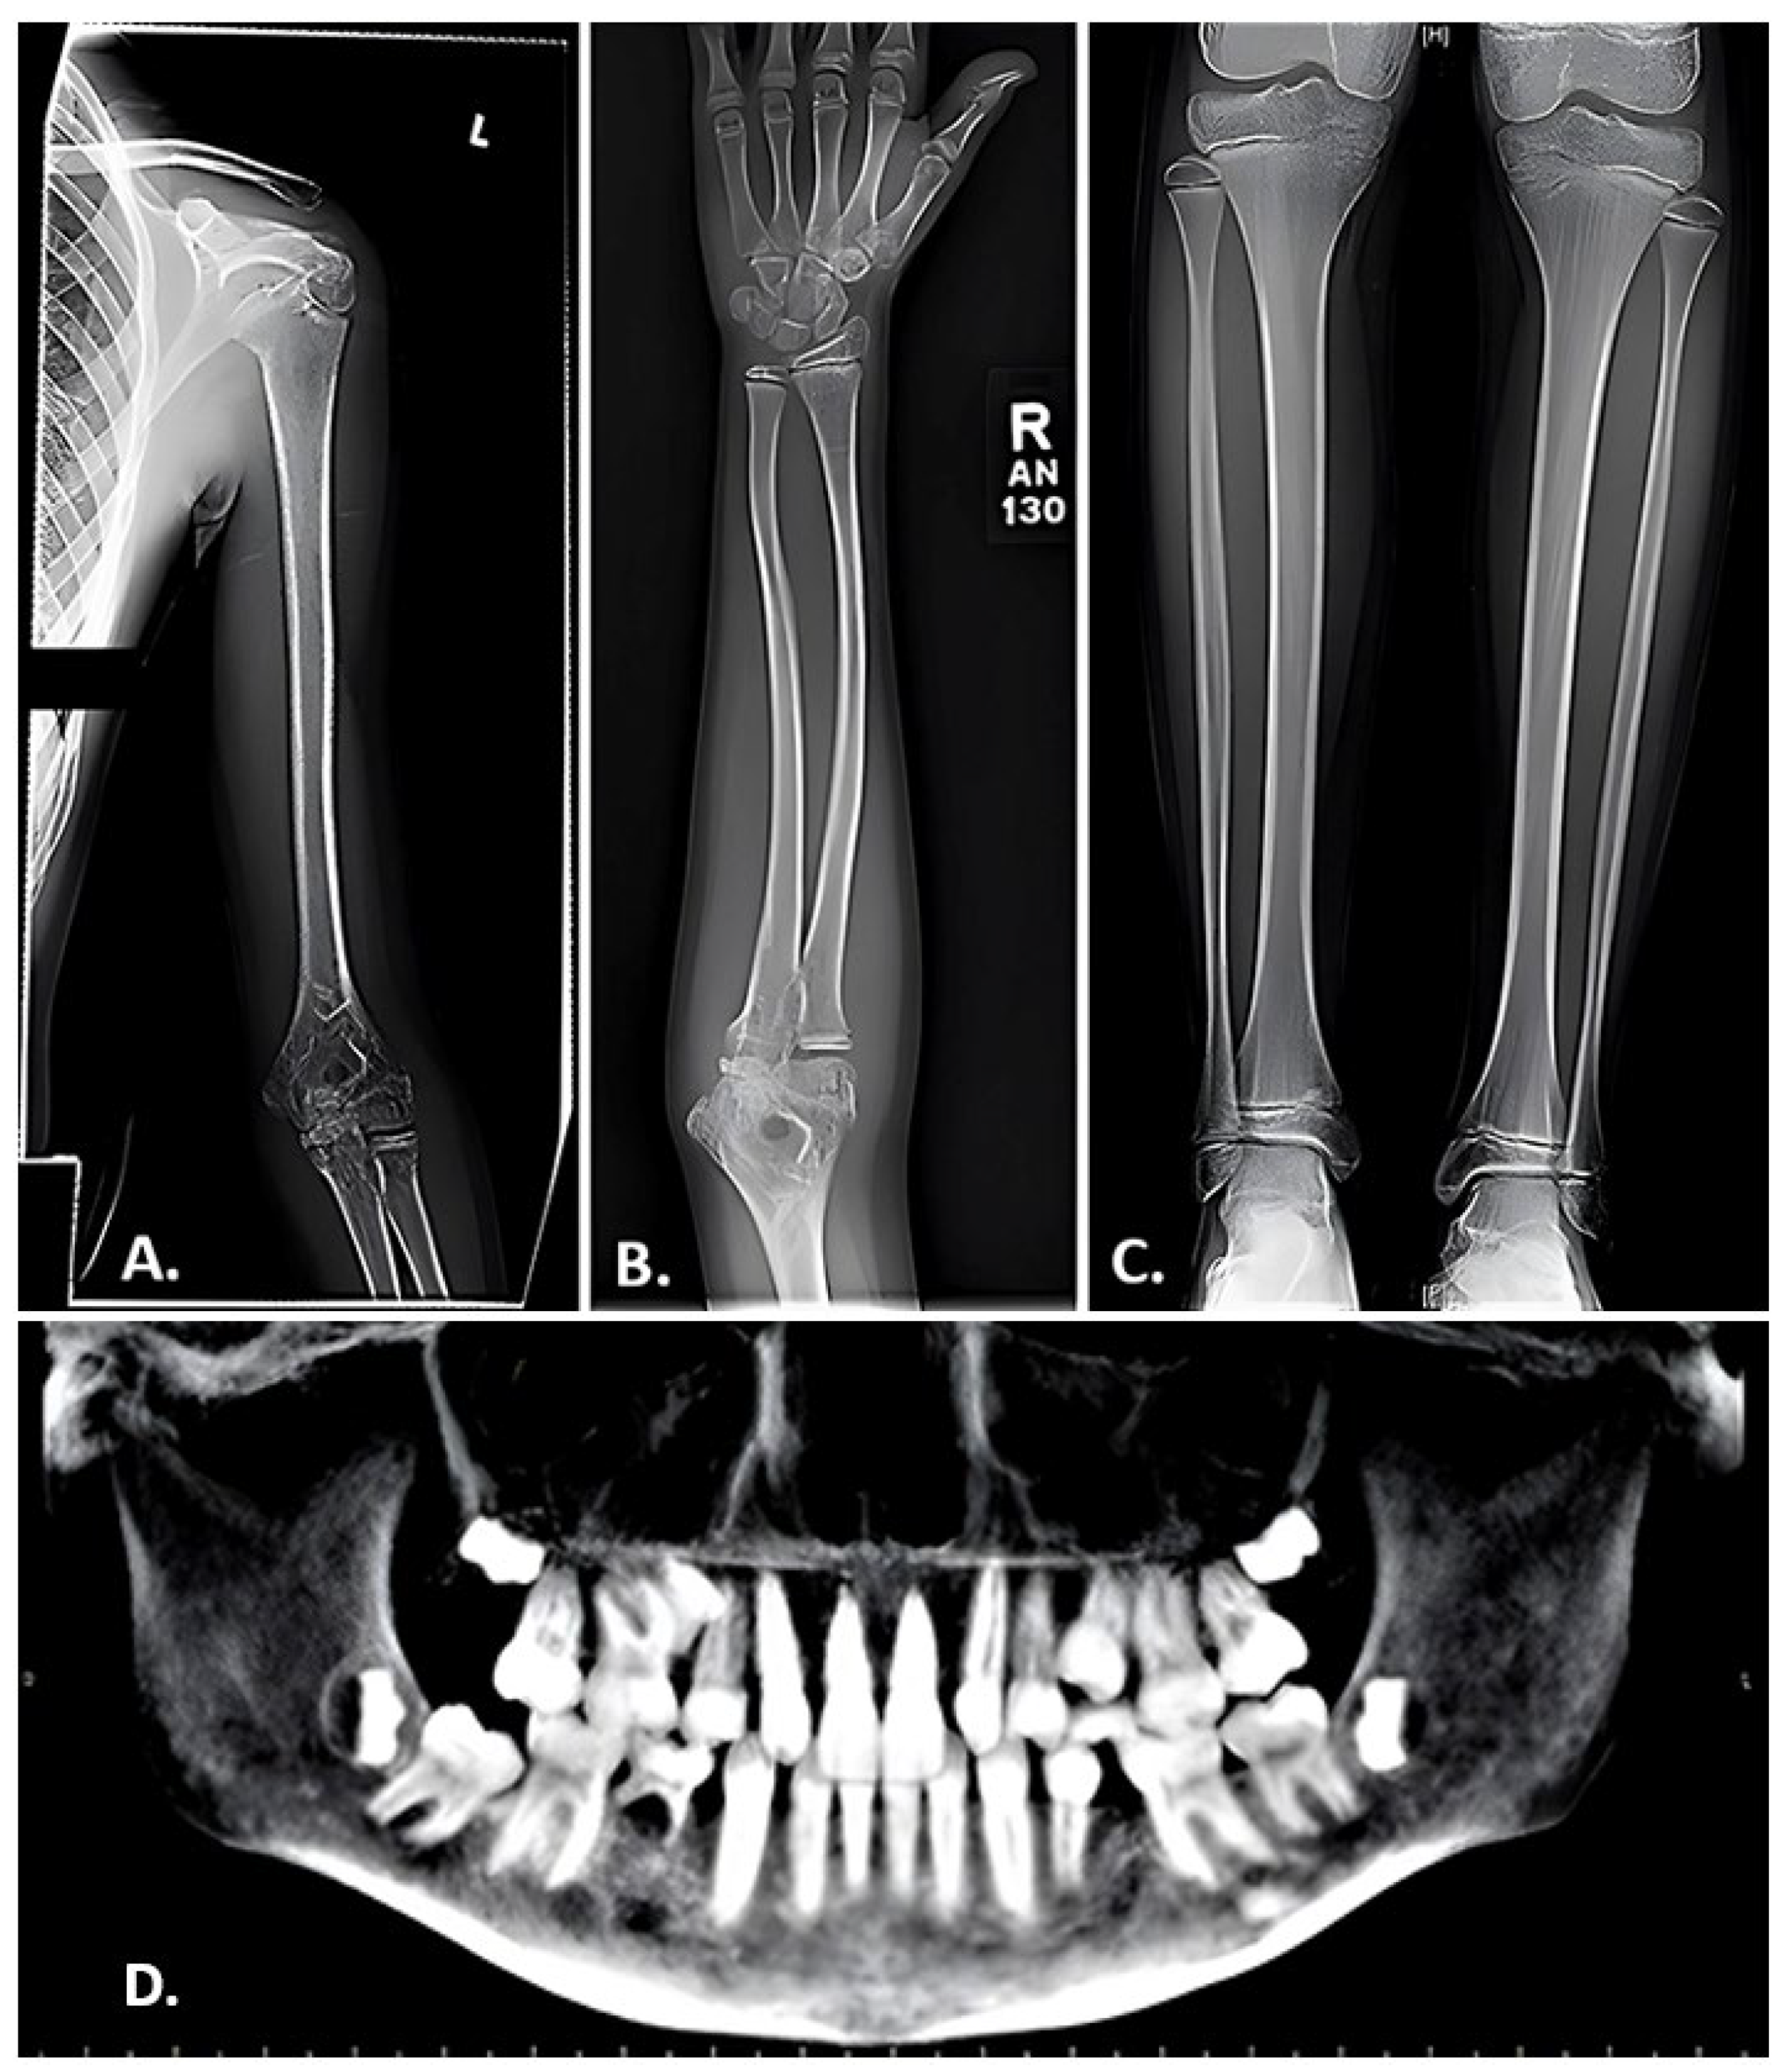

- Zhao, D.; Sun, L.; Zheng, W.; Hu, J.; Zhou, B.; Wang, O.; Jiang, Y.; Xia, W.; Xing, X.; Li, M. Novel mutation in LRP5 gene cause rare osteosclerosis: Cases studies and literature review. Mol. Genet. Genomics. 2023, 298, 683–692. [Google Scholar] [CrossRef]